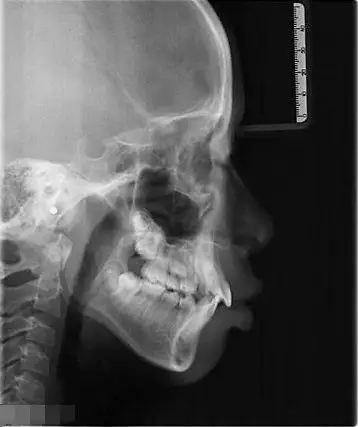

需要正颌吗?(内附侧面照及x光)

友们会看牙片吗求帮我看看这是骨性还是牙性地包天

你还看不懂x光片?徐医生带你全面解析

牙科治疗的颌面x光片.口腔正畸诊断

正畸前的侧面正畸前的牙齿由于我的牙齿状态比较差,上齿右5早期补过牙